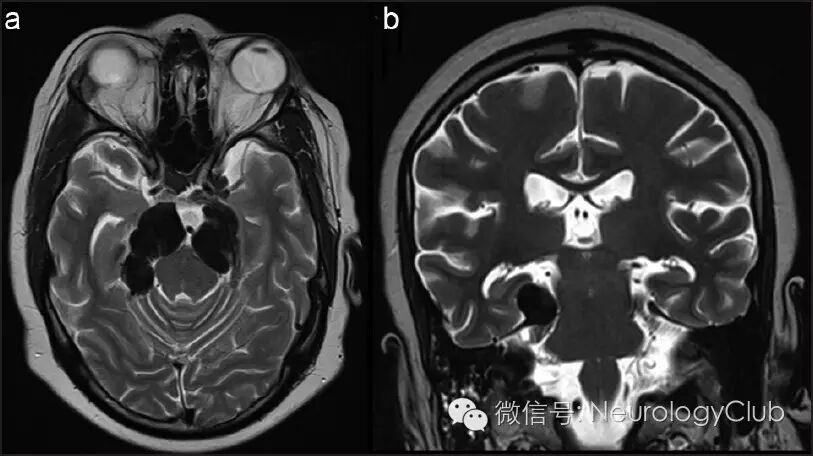

21岁男性,表现为进行性头痛,行走困难和视力、听力下降6年。查体发现患者双侧继发性视神经萎缩,双侧感音神经性耳聋和痉挛性四肢瘫痪。头颅MRI可见中和后颅窝多发结节样病灶,增强后均匀强化。基底脑膜弥漫增厚并强化,一直延伸至颈部(图1)。结节样病灶在T1WI上等信号,T2WI上低信号(图2)。双侧上颌窦可见类似病灶。胸部CT和腹部超声均正常。

(图2:治疗前的T2WI。可见病灶呈等至低信号,伴有明显的脑干受压)